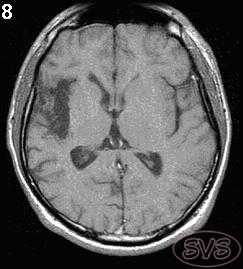

Ранние дегенеративные изменения в мозге возникающие в период беременности, пери- или постнатально проявляются виде порэнцефалии, энцефаломаляции и т.д., что достаточно хорошо выявляется с помощью МРТ. Посттравматические рубцово-атрофические изменения у взрослых часто могут сопровождаться эпилепсией (рис 8).

Рис 8. Посттравматические рубцово-атрофические изменения в правой височной доле с энцефаломаляцией (Т1-взв. изображение).

МРТ головного мозга при туберозном склерозе. Участки изменения МР-сигнала неправильной формы в коре и подкорковом белом веществе — так называемые корковые туберсы.